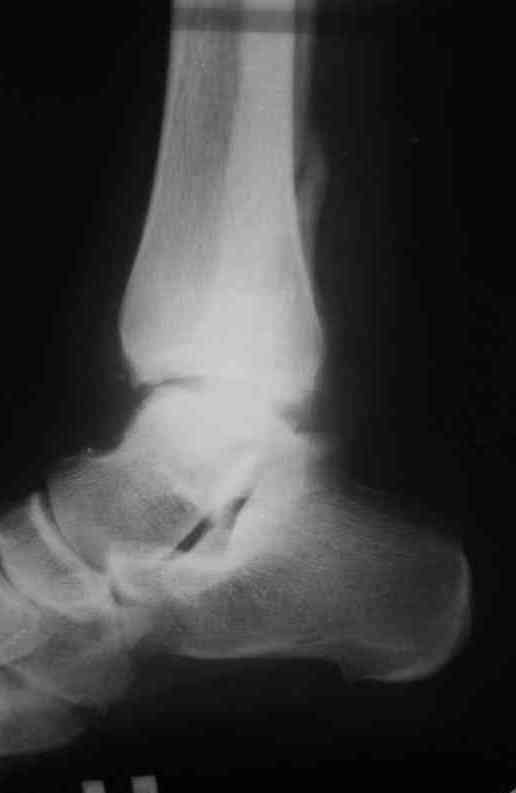

Неправильно консолидированный перелом лодыжек |

Обратился больной 23 года, травма 4 месяца назад - закрытый перелом наружной, внутренней лодыжки правой голени. Лечился консервативно, гипсовой иммобилизацией 8 недель, после снятия последней прошел курс восстановительного лечения. Беспокоят боли в области правого голеностопного сустава больше в проекции внутренней лодыжки, к вечеру. Отечность области сустава при физических нагрузках.

Походка не изменена. Контуры правого голеностопного сустава сглажены. Имеется вальгусная установка правой пяточной кости. Объем движений в голеностопном суставе подошвенное / тыльное сгибание 50/0/80, безболезненные. Посоветуйте что делать в данной ситуации.

Мне видится следующий вариант решения данной деформации: Восстановление нормальной анатомии голеностопного сустава - остеотомия малоберцовой кости и внутренней лодыжки, удалить все рубцы из области дистального межберцового синдесмоза, восстановить длину и устранить ротационное смещения наружной лодыжки.( встанет ли таранная кость на место?), фиксация наружной лодыжки пластиной, внутренней - винтами, дистального межберцового синдесмоза винтом. ЭОПом не располагаем. Что вы посоветуете? Где могут быть - технические трудности, <подводные камни>.